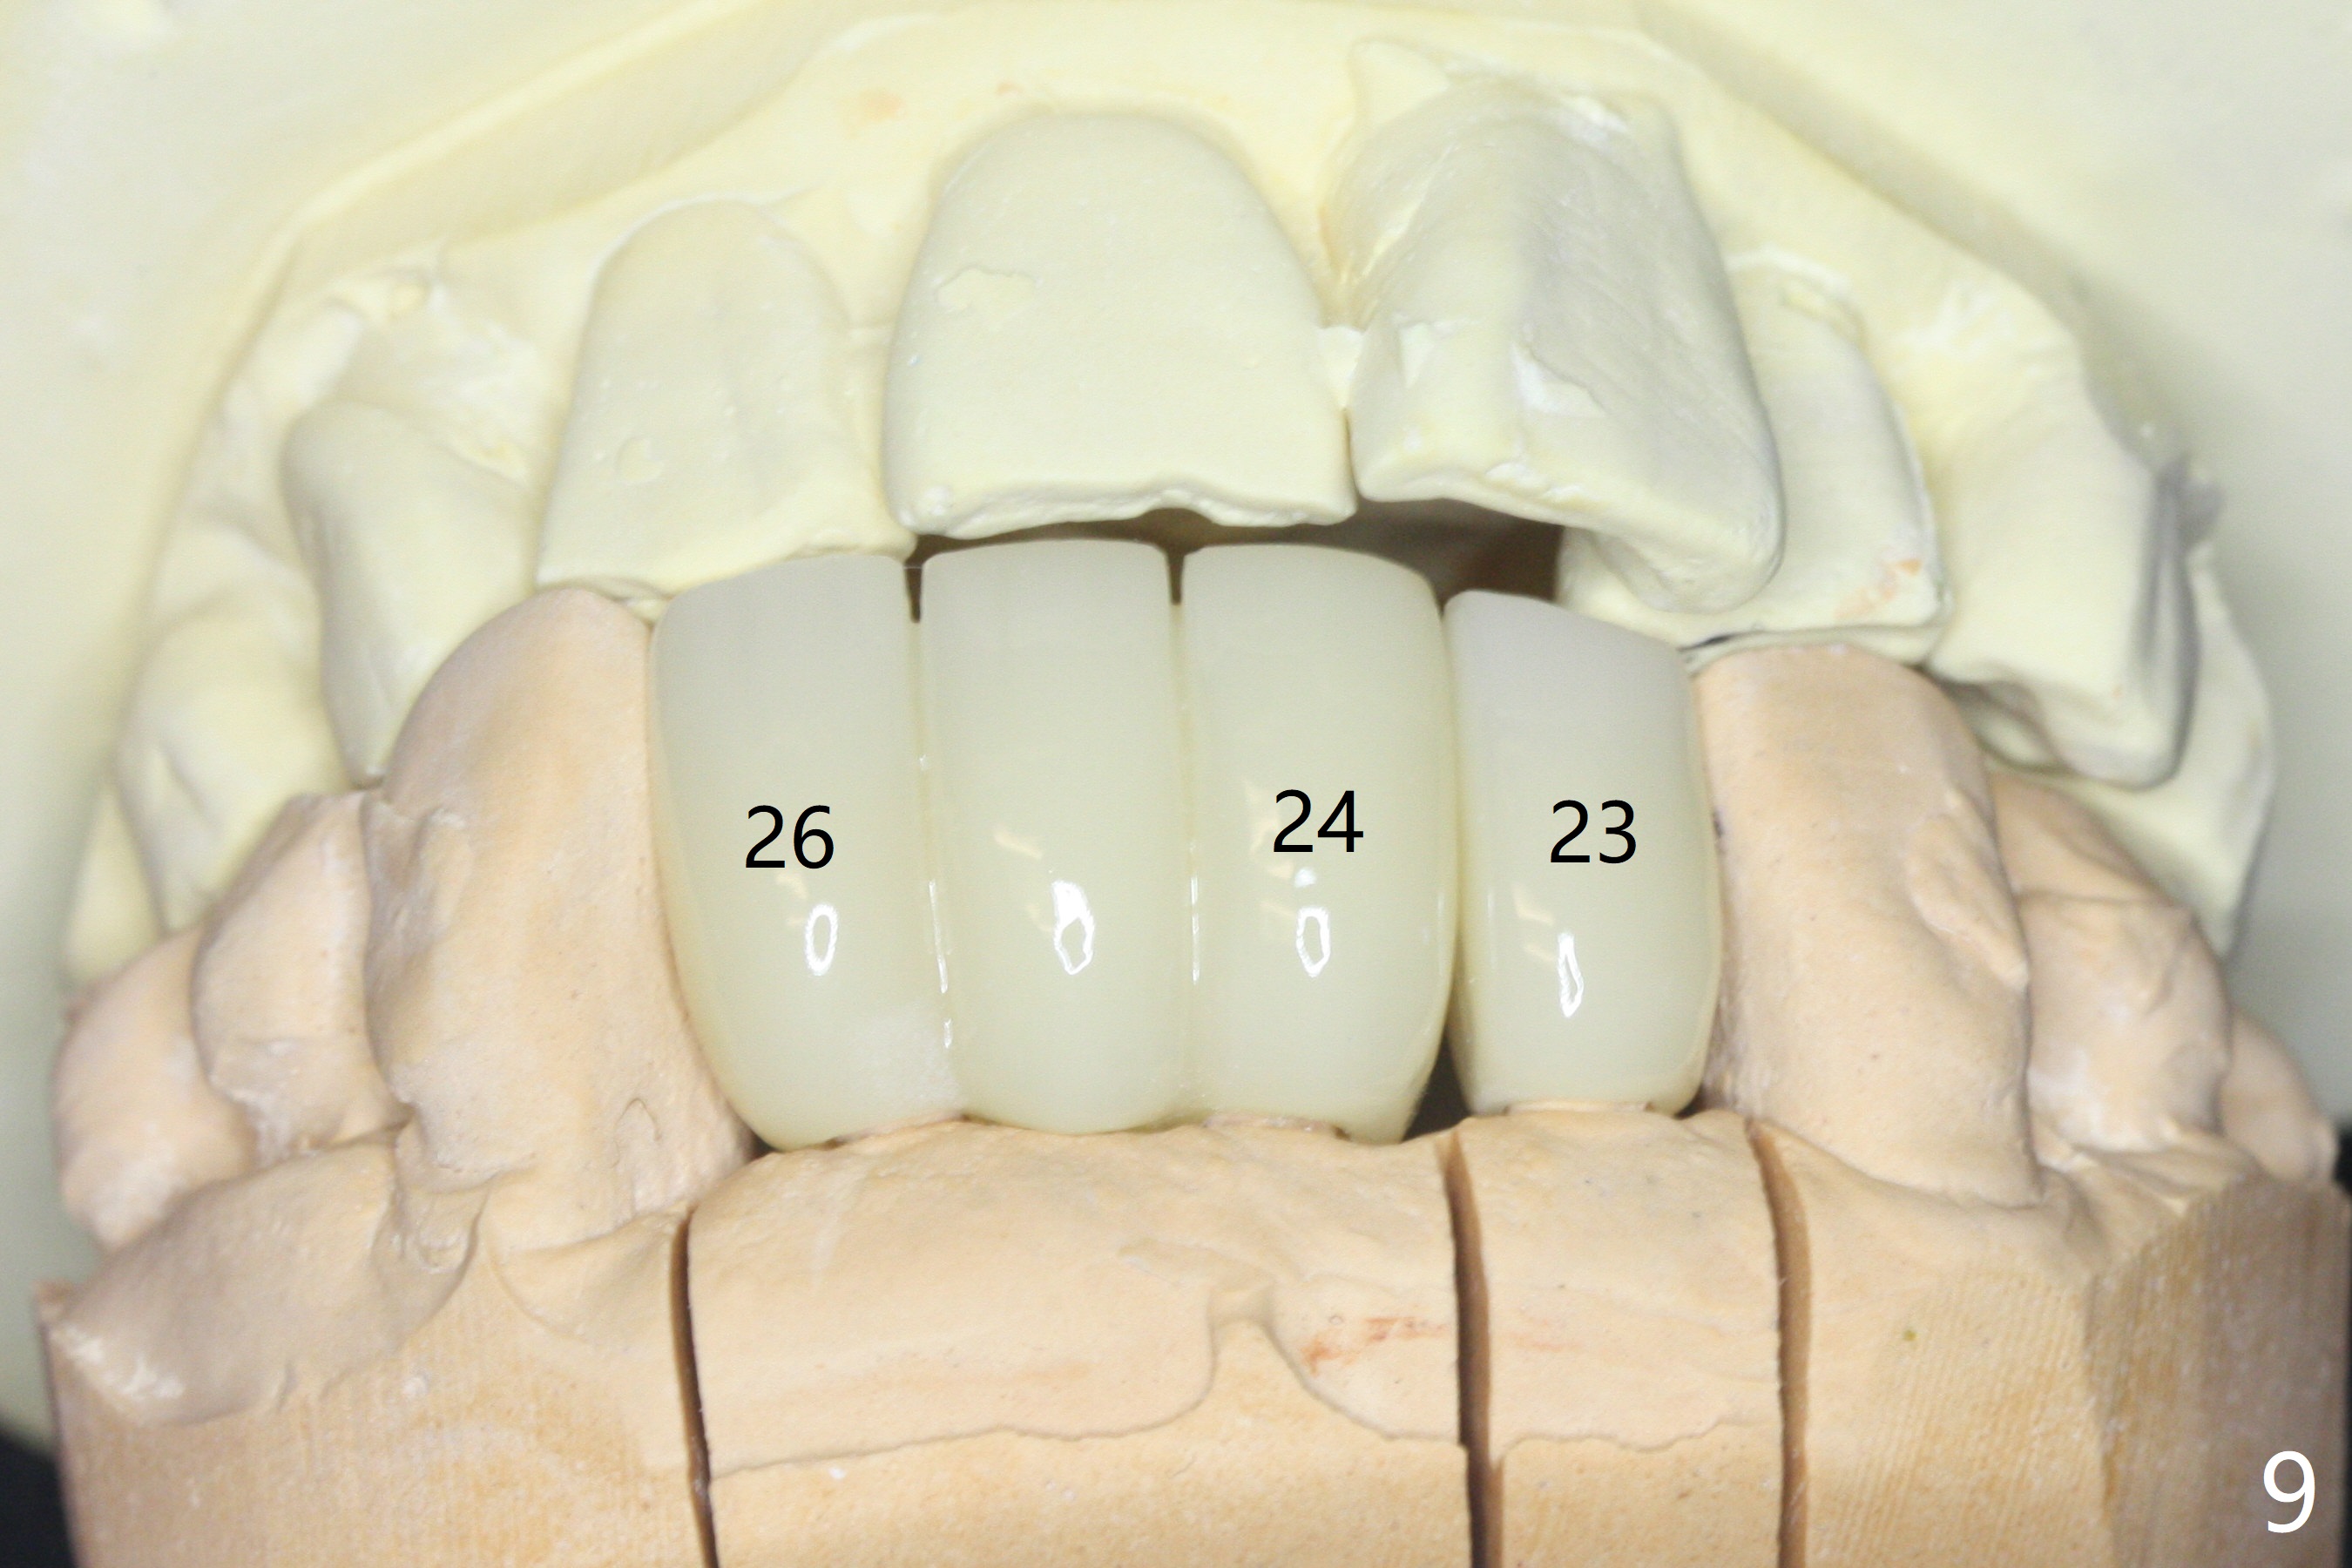

When the patient returns, the tooth #24 has exfoliated, while the ones at #25 and 26 has mobility III (Fig.1). The patient requests the tooth #23 extraction (Fig.2), but not #27. After SRP and extraction, osteotomy is initiated mesial to the sockets #23,25 and 26 (Fig.3,4) with intention to place 3 1-piece implants for 3 incisor crowns (Fig.5,6). Following Vanilla graft (Fig.5 *) a splinted provisional is fabricated to close the sockets (Fig.6). Peri-implant spaces close 5.5 months postop (Fig.7). Impression is taken after reprep for margin and parallelism (Fig.8). The final restoration consists of #23 single unit crown and #24-26 3-unit FPD (Fig.9). It appears that 2.5 mm 1-piece implants are not too small for the lower incisors (Fig.10-12), especially the central one (Fig.11). There may be perforation in the apical half of the lingual plate (L in Fig.10). The patient is not pleased with the shade of the #24-26 3-unit FPD (Fig.13 (6 months post cementation)). There is metal show through the abutments (*).